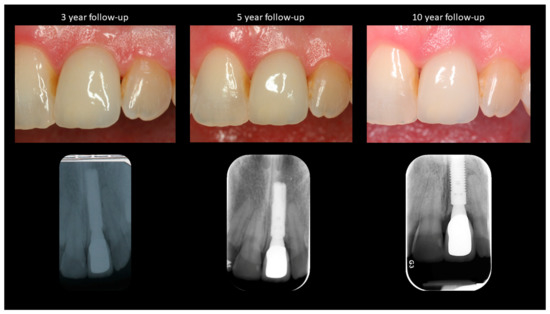

- T3—3-year follow-up.

- T4—5-year follow-up.

- T5—10-year follow-up.

| Soft Tissue Recession (in mm) | Bone Level Changes (in mm) | PES * | ||||

|---|---|---|---|---|---|---|

| Mesial Papilla | Midfacial | Distal Papilla | Mesial | Distal | ||

| T0 | - | - | - | - | - | 10 |

| T1 | 0.2 | −0.2 | 0.0 | 0 | 0 | 12 |

| T2 | 0.2 | −0.2 | 0.1 | −0.2 | −0.2 | 12 |

| T3 | 0.1 | −0.2 | 0.2 | −0.6 | −0.5 | 12 |

| T4 | 0.1 | −0.3 | 0.1 | −0.5 | −0.5 | 12 |

| T5 | 1.0 | −0.3 | 0.1 | −0.7 | −0.7 | 11 |